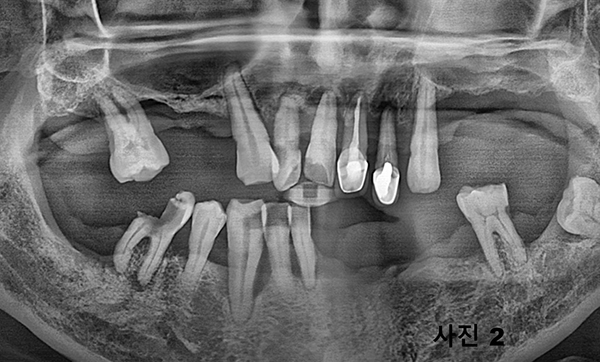

틀니를 상담하기 위해 내원한 50대의 환자로써 (사진1 ) 파노라마사진을 촬영하고 구강검진(사진2) 하여보니,

아직 나이도 젊고 일반 틀니로서는 기능회복이 어려울 것 같아 임플란트를 이용한 똑딱이 틀니를 설명하였다.

그러나 환자가 틀니 대신에 고정성 보철물을 문의하기에 환자의 구강상태, 전신 건강상태, 치료비의 감당능력을

서로 상의하고 상하악에 최소 4개씩 식립하고 풀아치 고정성 보철물을 제작하기로 하였다.

수술 당일 수면마취후 12개의 치아를 다 발치하고 상악에 5개 하악에 4개를 식립하고 (사진3) 왼쪽 마지막 어금니는 단단하여

살리면서 그 상태를 컴퓨터 스캐닝하여 본 병원에서 다음날 (사진4)와 같이 임시 고정성 보철물을 제작하여 심미적 기능과 저작기능을 제공하여 주었다.